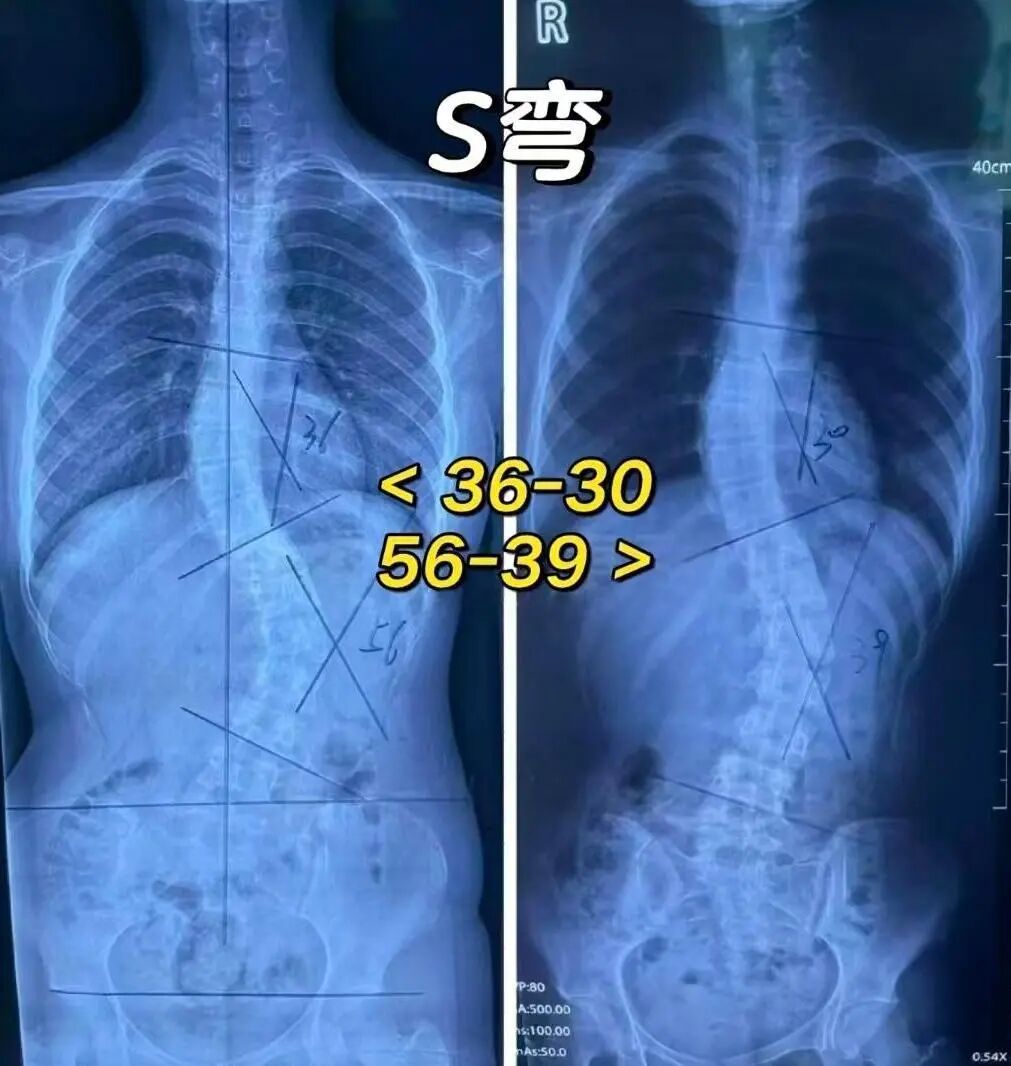

别再把孩子的“驼背”,当成小问题了

很多脊柱侧弯,都是从“看起来只是姿势不好”开始的。

但其实,脊柱侧弯并不只是“坐姿不正”。它是一种脊柱已经发生结构改变的情况,不仅会向一侧弯曲,还会伴随一定程度的旋转,久而久之形成明显的体态异常。